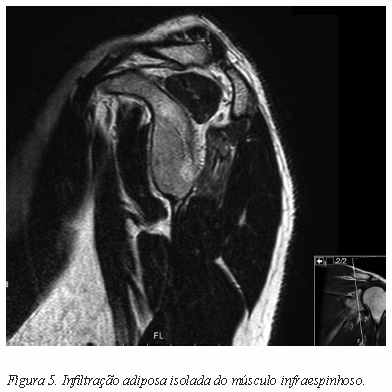

A ressonância magnética (RM) é o exame ideal para visualizar o trajeto do nervo bem como identificar massas ou outras lesões ocupando espaço32-34. Permite excelente avaliação do labrum, quistos associados, tendões da coifa dos rotadores e qualidade dos músculos, incluindo a infiltração adiposa e a atrofia35 (Figura 5).

A electromiografia e o estudo da velocidade de condução do nervo são instrumentos fundamentais no estudo da patologia do nervo supra-escapular23. Apesar da sensibilidade e especificidade do exame ser ainda um assunto em debate, é profundamente dependente do tipo de lesão em causa mas também da experiência do executante5, 23, 36. A electromiografia está indicada na presença de: dor no ombro continua, persistente, sem outra explicação; atrofia e fraqueza dos músculos supraespinhoso e infraespinhoso sem evidência de rotura da coifa ou infiltração adiposa; edema dos músculos observado em RM sem evidência de rotura da coifa5, 37. Está indicada ainda na presença de quisto associado a rotura maciça da coifa com retração franca ou a lesão labral para excluir concomitante lesão do nervo supraescapular10.